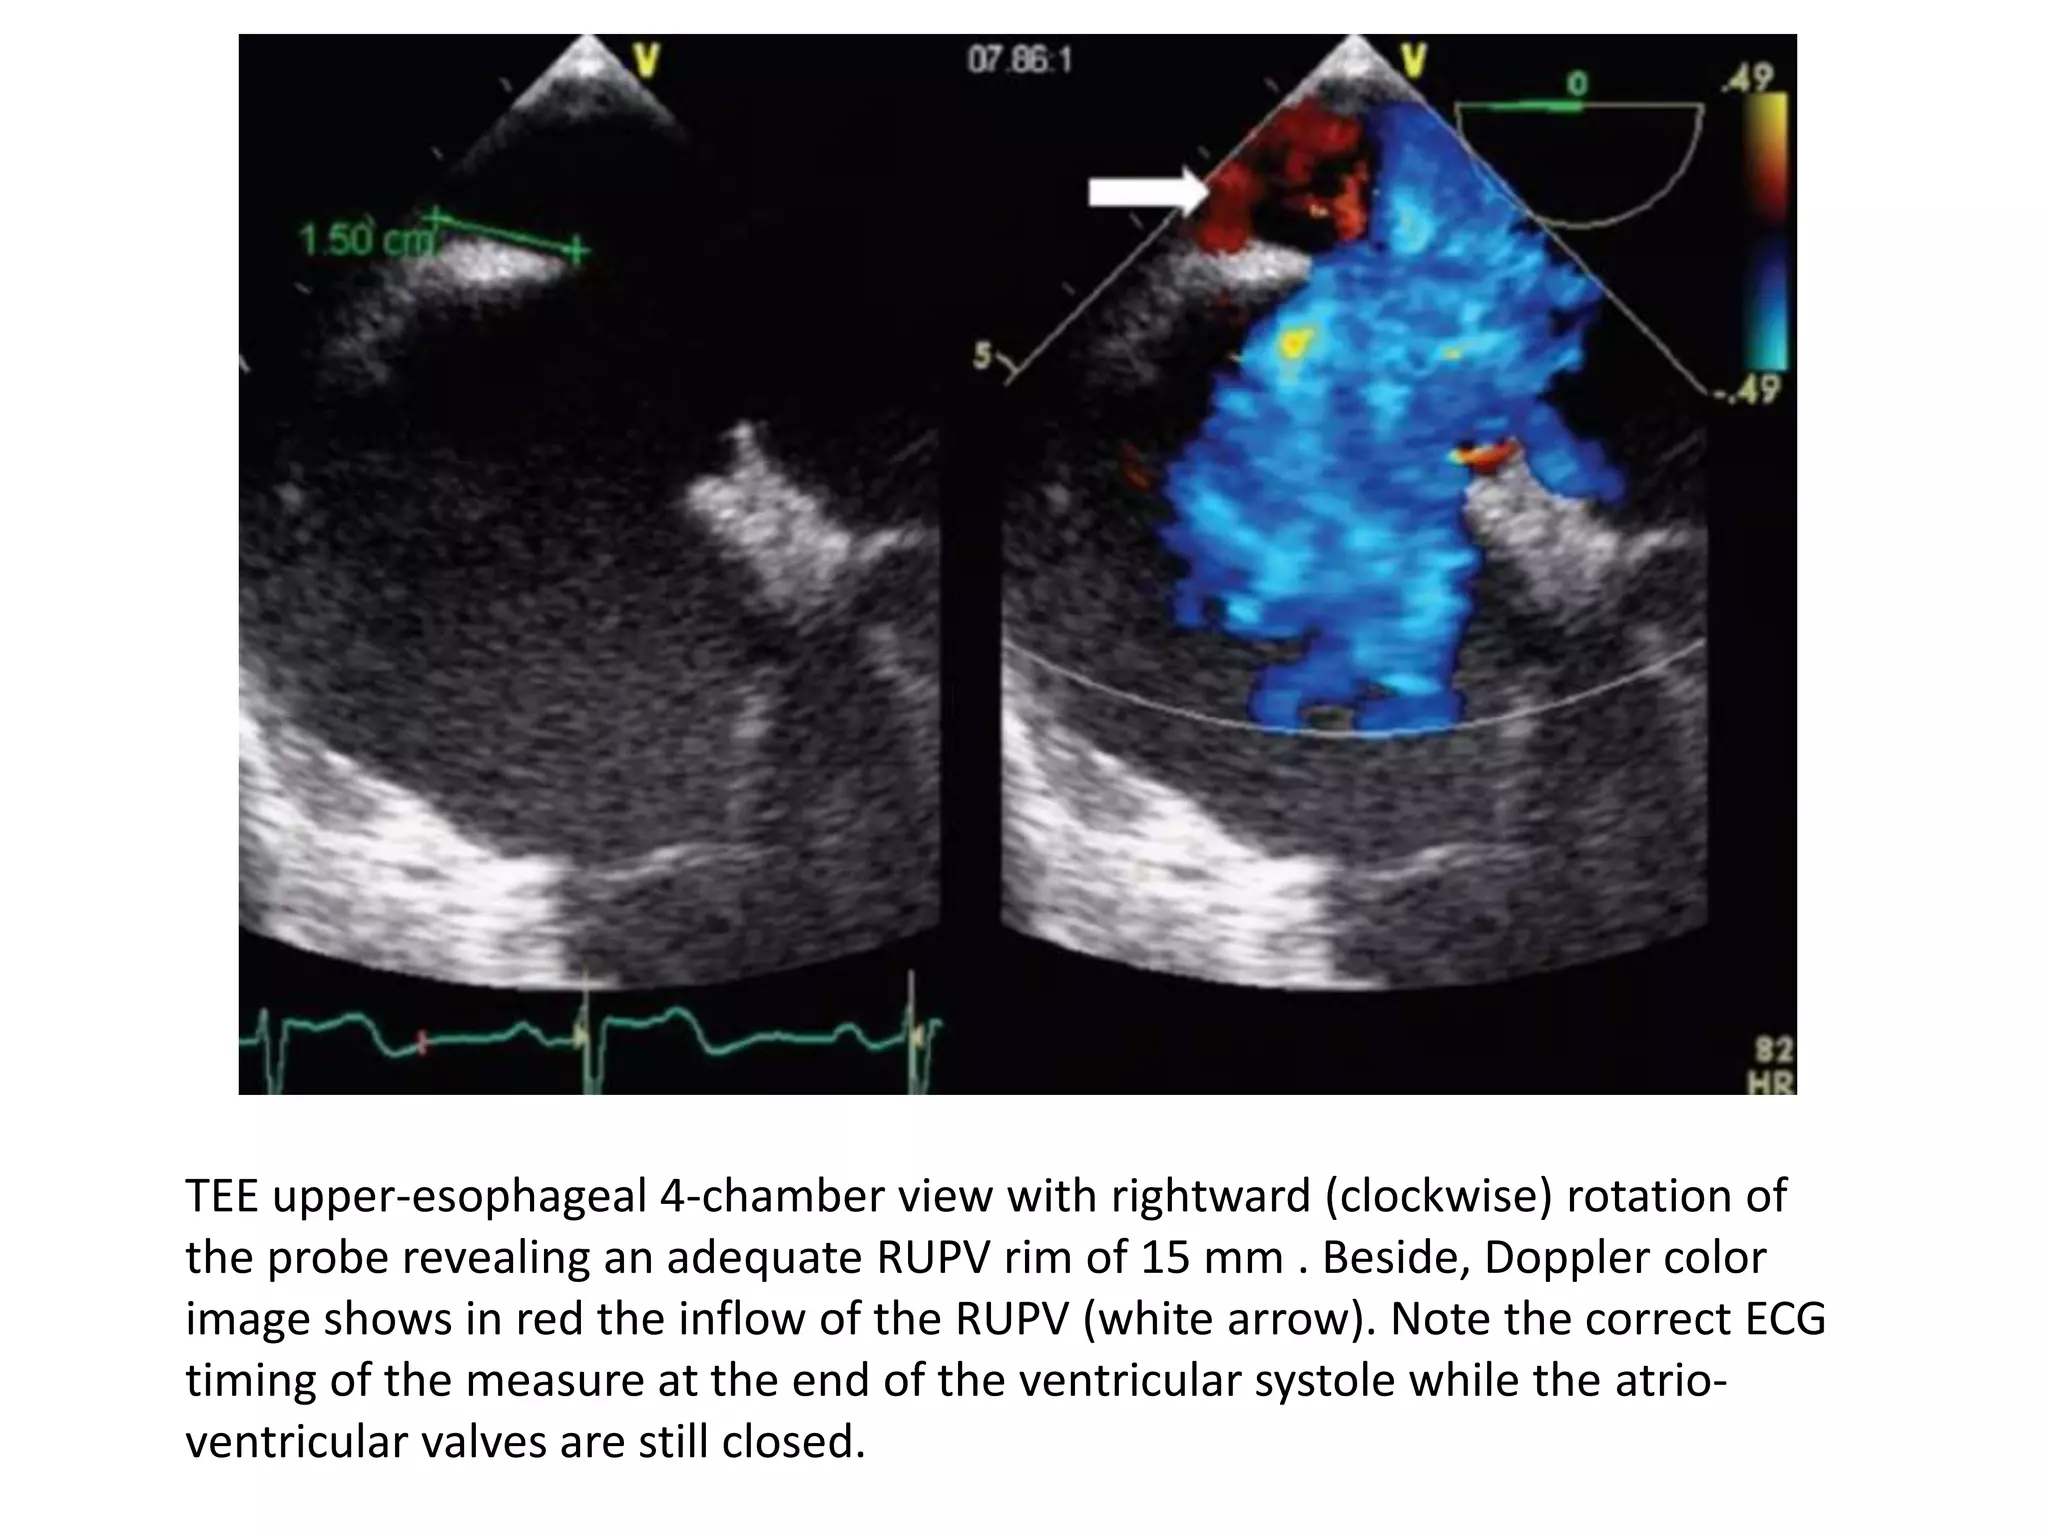

TEE upper-esophageal 4-chamber view with rightward (clockwise) rotation of

the probe revealing an adequate RUPV rim of 15 mm . Beside, Doppler color

image shows in red the inflow of the RUPV (white arrow). Note the correct ECG

timing of the measure at the end of the ventricular systole while the atrio-

ventricular valves are still closed.

TEE upper-esophageal 4-chamberview with rightward (clockwise) rotation of the probe revealing an adequate RUPV rim of 15 mm . Beside, Doppler color image shows in red the inflow of the RUPV (white arrow). Note the correct ECG timing of the measure at the end of the ventricular systole while the atrio- ventricular valves are still closed.